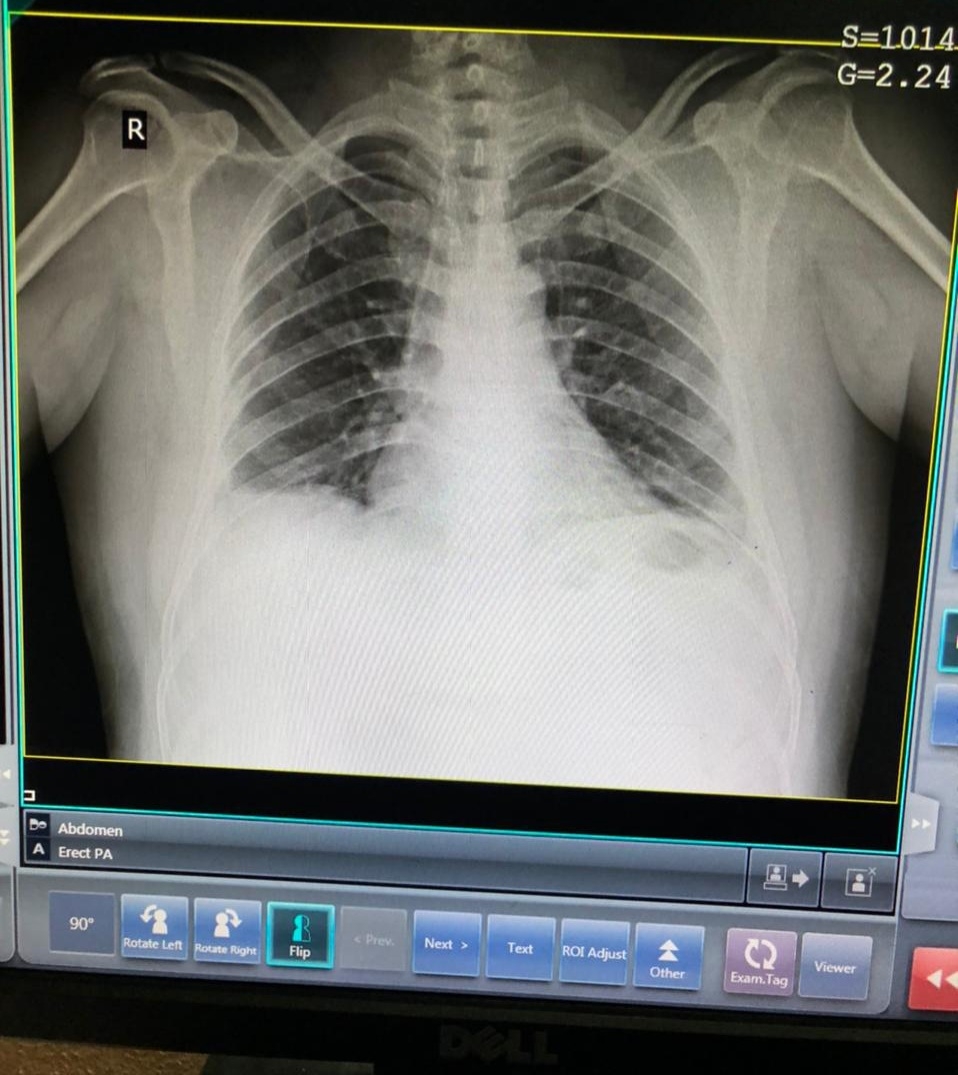

37 year old male with acute pancreatitis

INVESTIGATIONS

PROVISONAL DIAGNOSIS :- ACUTE PANCREATITIS